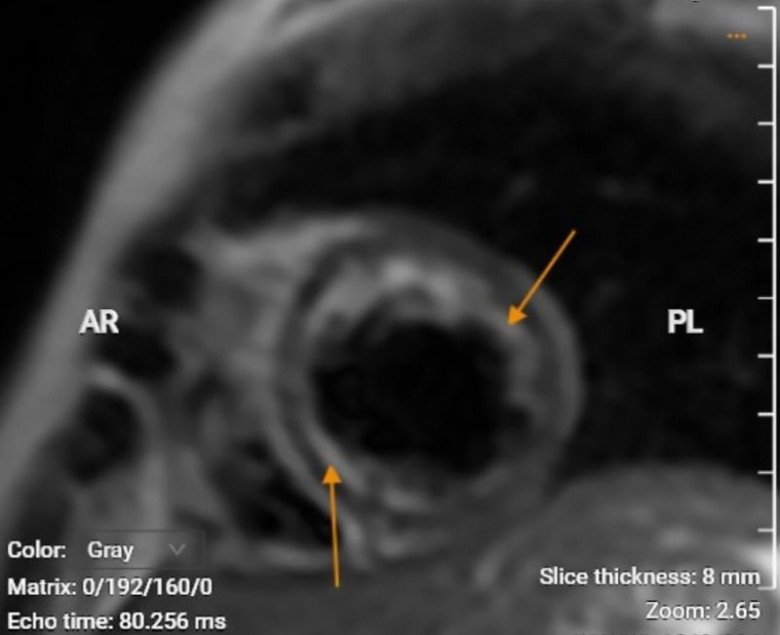

BSCK II Nguyễn Quang Minh - Trưởng khoa Khám bệnh (Bệnh viện Medlatec) cho biết, kết quả chụp MRI tim cho thấy bệnh nhân có nhiều vấn đề ở tim, được kết luận là suy tim do viêm cơ tim sau sốc phản vệ. Các chuyên gia đã hội chẩn, tư vấn hướng điều trị và theo dõi ca bệnh.

Bác sĩ khuyến cáo, khi có các dấu hiệu bất thường, bạn cần đến các cơ sở y tế uy tín để được thăm khám kịp thời và đưa ra hướng điều trị phù hợp. Trong đó các kỹ thuật chẩn đoán, chụp cộng hưởng từ sẽ giúp chẩn đoán, phân loại và tiên lượng di chứng tổn thương tim sau sốc phản vệ.

“Đây là phương pháp được đánh giá là giải pháp thay thế không xâm lấn hữu ích nhờ khả năng mô tả đa chiều về đặc tính mô học, không chỉ cung cấp thông tin chẩn đoán phân biệt tình trạng viêm cơ tim mà còn truyền tải thông tin về giai đoạn và tiên lượng bệnh”, bác sĩ Minh cho hay.